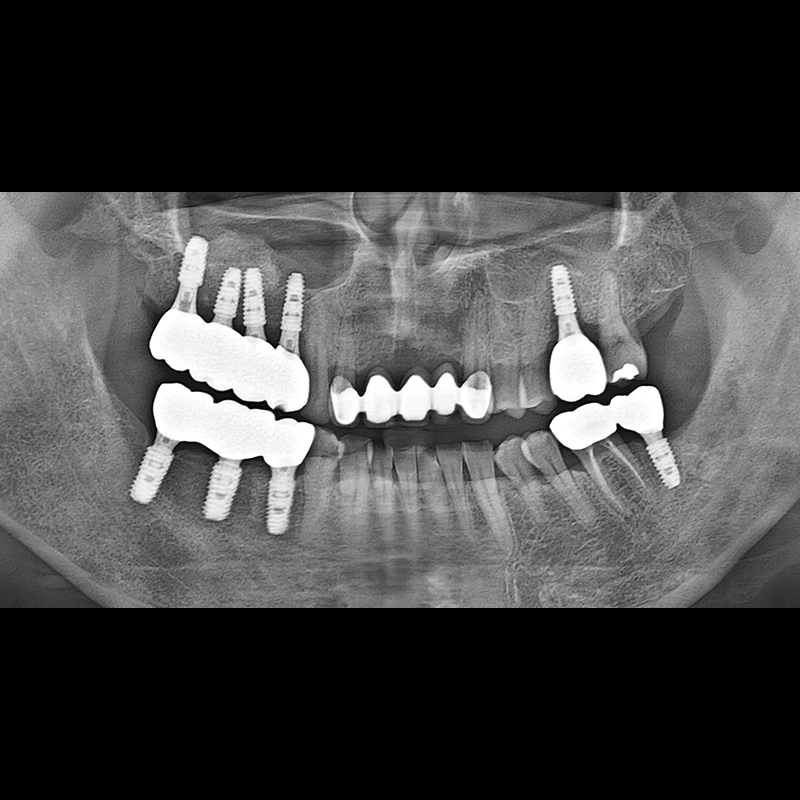

BEFORE AFTER

Implant before and after 2025.05.30

Implants were placed in the missing tooth and in the tooth position where it was difficult to save.